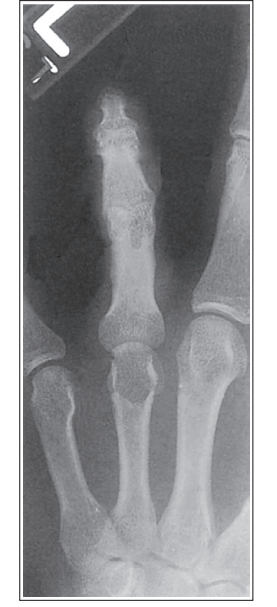

Unequal concavity between phalanges and MCs

Hand was slightly externally rotated

What is wrong with this oblique hand?

Unequal concavity and greater concavity and soft tissue width is closer to the thumb

External rotation of thumb